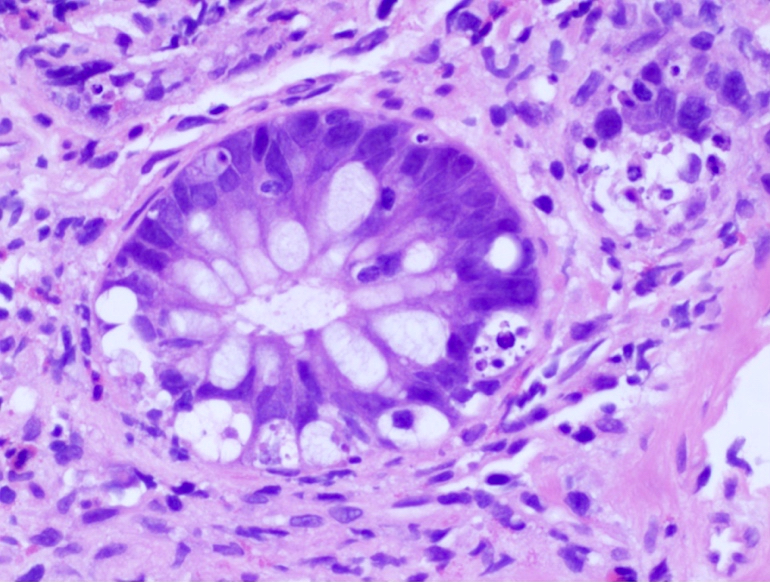

- Characteristic histologic features include crypt apoptosis, crypt dropout and ulceration (Biol Blood Marrow Transplant 2015;21:589)

- Endocrine cell nests may be seen (Am J Surg Pathol 2013;37:1319)

- Grade I: crypt apoptosis without crypt dropout

- Grade II: single crypt dropout

- Grade III: contiguous crypt dropout

- Grade IV: diffuse crypt dropout with ulceration

Microscopic (histologic) images